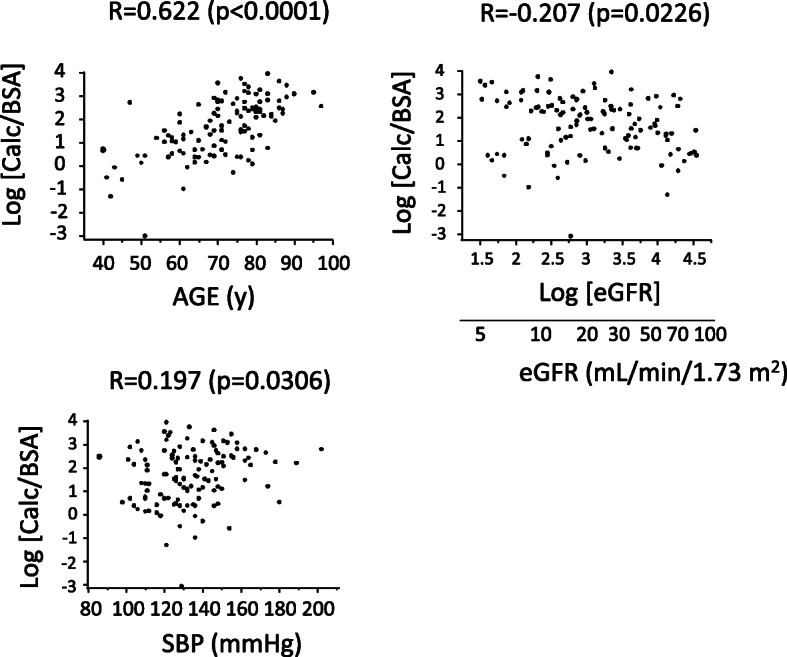

The relationship between log [Calc/BSA] and either of age, log [eGFR], SBP, use of warfarin, use of diuretics, presence of malignancy, or use of ACEI and/or ARB was investigated by univariate linear regression analyses as shown in Fig. 2 and Fig. 3. Then, log [Calc/BSA] was adjusted by clinical parameters in multivariate linear regression analyses as shown in each model in Table 2.

Fig. 2.

Univariate analyses of age, eGFR, and systolic blood pressure (SBP) on the day of CT scan against vascular calcification volume. In univariate analyses, phosphate concentration and malignancy were not associated with log [Calc/BSA] (p = 0.3768 and p = 0.8414, respectively). Male sex, diabetes and diuretics were significantly associated with log [Calc/BSA] (p = 0.0002, p = 0.0013 and p = 0.0020, respectively). BSA, body surface area calculated with Fujimoto’s formula; Calc, calcification volume; CT, computed tomography; eGFR, estimated glomerular filtration rate; SBP, systolic blood pressure

The characteristics of the 121 patients (mean age, 71 ± 12 years; 72 men) included in the analysis are provided in Table 1A. Among these patients, the median Calc was 8.94 (3.26 - 18.9) mL, and the median Calc/BSA was 5.62 (2.01 - 12.7) mL/m2. The mean log [Calc/BSA] was 1.67 ± 1.20. The mean log [eGFR] was 3.1 ± 0.8, which corresponds to an eGFR of 20.2 (11.8 - 40.3) mL/min/1.73m2. The relationships between log [Calc/BSA] and either of age, log [eGFR], SBP, warfarin, diuretics, malignancy or ACEI/ARB were investigated. Log [Calc/BSA] was significantly associated with age (p < 0.0001), log [eGFR] (p = 0.0226) or systolic blood pressure (p = 0.0306) as shown in Fig. 2. The association of warfarin with log [Calc/BSA] was significant (p = 0.0287). The association of ACEI/ARB with log [Calc/BSA] was marginally significant (p = 0.0586) (Fig. 3) Moreover, the association of diuretics with log [Calc/BSA] was significant (p = 0.0020). The association of malignancy with log [Calc/BSA] was not significant (p = 0.8414). In univariate analyses, the difference of the median values of log [Calc/BSA] was 1.10 with or without warfarin (Fig. 3). That was 0.53 with or without ACEI/ARB (Fig. 3).